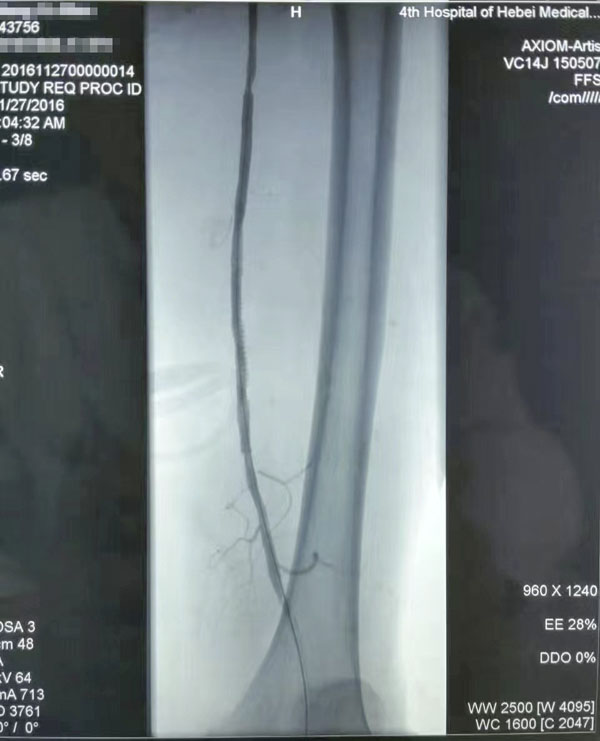

介入治疗前后对比

糖尿病足重在预防,而预防和治疗下肢血管病变是防治糖尿病足的有效措施。下肢血运重建是糖尿病下肢血管病变治疗的根本,采用球囊扩张开通狭窄或闭塞的下肢动脉(介入治疗),恢复直达足部的血流,是治疗糖尿病下肢血管病变的根本措施,具有立竿见影的效果。这也是近年来在糖尿病足诊治方面取得的又一新进展,为广大糖尿病下肢血管病变患者解除了痛苦,使糖尿病足患者截肢率由34%降至4%。世界防治糖尿病日到来之际,希望广大糖尿病患者关注糖尿病下肢血管病变,保护自己的双足,做到早发现、早治疗,提升幸福感,快乐每一天。